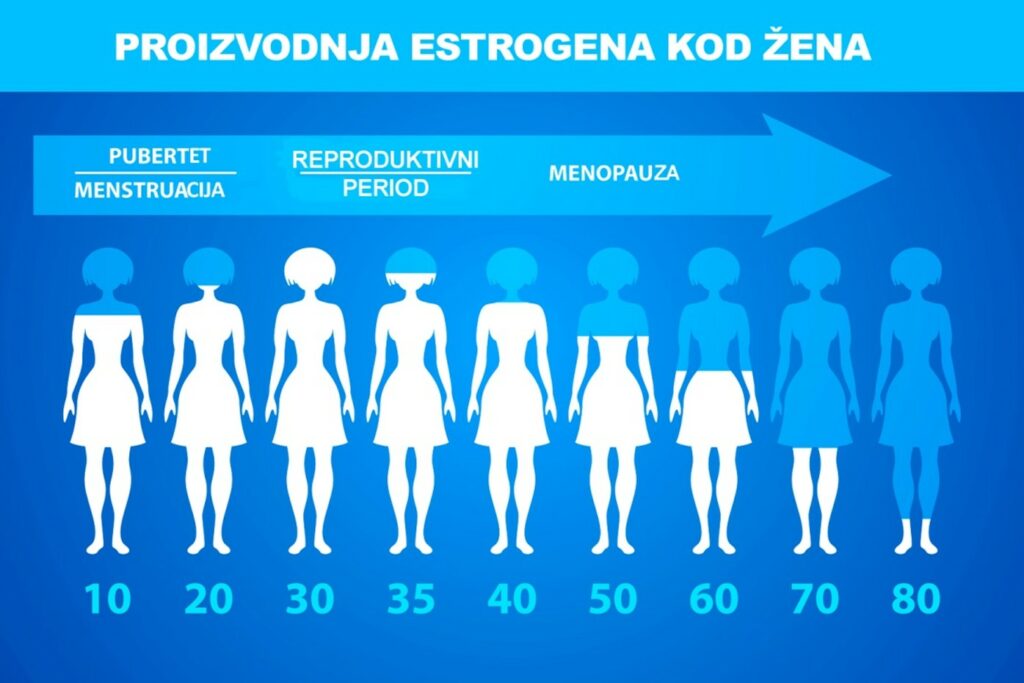

Promene koje smatramo „menopauzom“ dešavaju se kada naši jajnici više ne proizvode dovoljne nivoe hormona što umanjuje njihovu aktivnost, a proizvodnja jajnih ćelija se smanjuje i potpuno prestaje. Jajnici su reproduktivne žlezde koje proizvode ženske hormone estrogen i progesteron, koji regulišu menstrualni ciklus i utiču na reproduktivnu sposobnost žena. Pored ovih tzv. ženskih hormona, u ženskom telu se takođe proizvode i androgeni – koji se često nazivaju „muškim hormonima“ (testosteron i dehidroepiandrosteron – DHEA), ali u manjim količinama nego kod muškaraca. Tokom menopauze, nivo estrogena i progesterona se drastično smanjuje, dok se nivo muških hormona ne menja ili mogu biti u blagom porastu.

Menopauzu posebno karakteriše nagli pad estrogena, hormona koji je do tada igrao ključnu ulogu u očuvanju zdravlja ženskog organizma.

Estrogen je neophodan za regulaciju širokog spektra funkcija, uključujući i metabolizam masti. Pored toga, estrogen pomaže u regulisanju metabolizma lipida u jetri. Kao rezultat toga, pad nivoa estrogena tokom menopauze dovodi do višeg nivoa LDL holesterola i triglicerida.